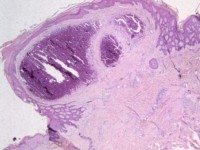

De epidermis is intact met centraal enige acanthose. In de dermis worden grote en ook kleinere compacte kalkhaarden aangetroffen, waarbij aan de rand van vooral de kleinere kalkdeposities een histiocytaire granulomateuze reactie wordt gezien, met histiocytaire reuslcelformatie. Kleuring op micro-organismen negatief.